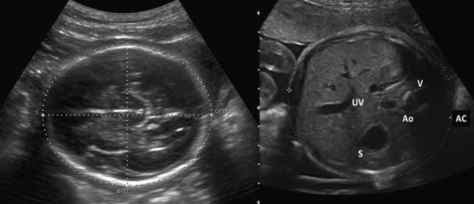

Ультразвуковий скринінг (УЗД експертного рівня) плода у І триместрі вагітності: (термін вагітності 11 – 14 тижнів, оптимально 12-13 тижнів).

При ультразвуковому скринінговому дослідженні у I триместрі ведеться пошук ультразвукових маркерів хромосомної патології: вимірюється товщина комірцевого простору (Nuchal Nranslucency scan), оцінюється наявність носової кістки, кровоплин в венозній протоці та на тристулковому клапані.

При збільшені товщини комірцевого простору (NT), відсутності носової кістки, патологічного кровотоку в венозній протоці, на тристулковому клапані в серці підвищується рівень ризику виникнення генетичних захворювань (в першу чергу синдром Дауна – трисомія 21 пари хромосом). Також проводиться скринінг анатомічних аномалій плода (вроджених вад).

Ультразвукове дослідження підтверджує розвиток та визначає розміри плоду, з встановленням найбільш точного гестаційного віку плоду та дати пологів.